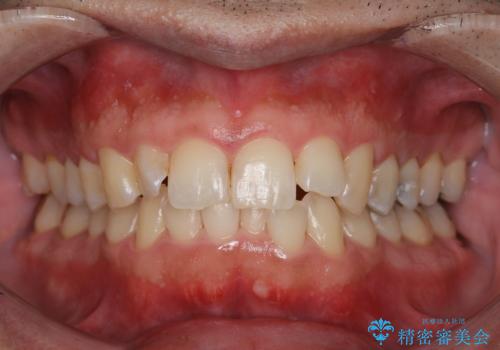

エアフローワンによるクリーニング

極小のパウダーと水を噴霧することで、歯や歯ぐきに対する負担を少なく、歯磨きでは落とすことができない汚れや着色などを除去することができます。

また、クリーニングで除去しにくい歯と歯の間の着色や矯正装置の周りなどにも対応しており、効率的に除去することができます。